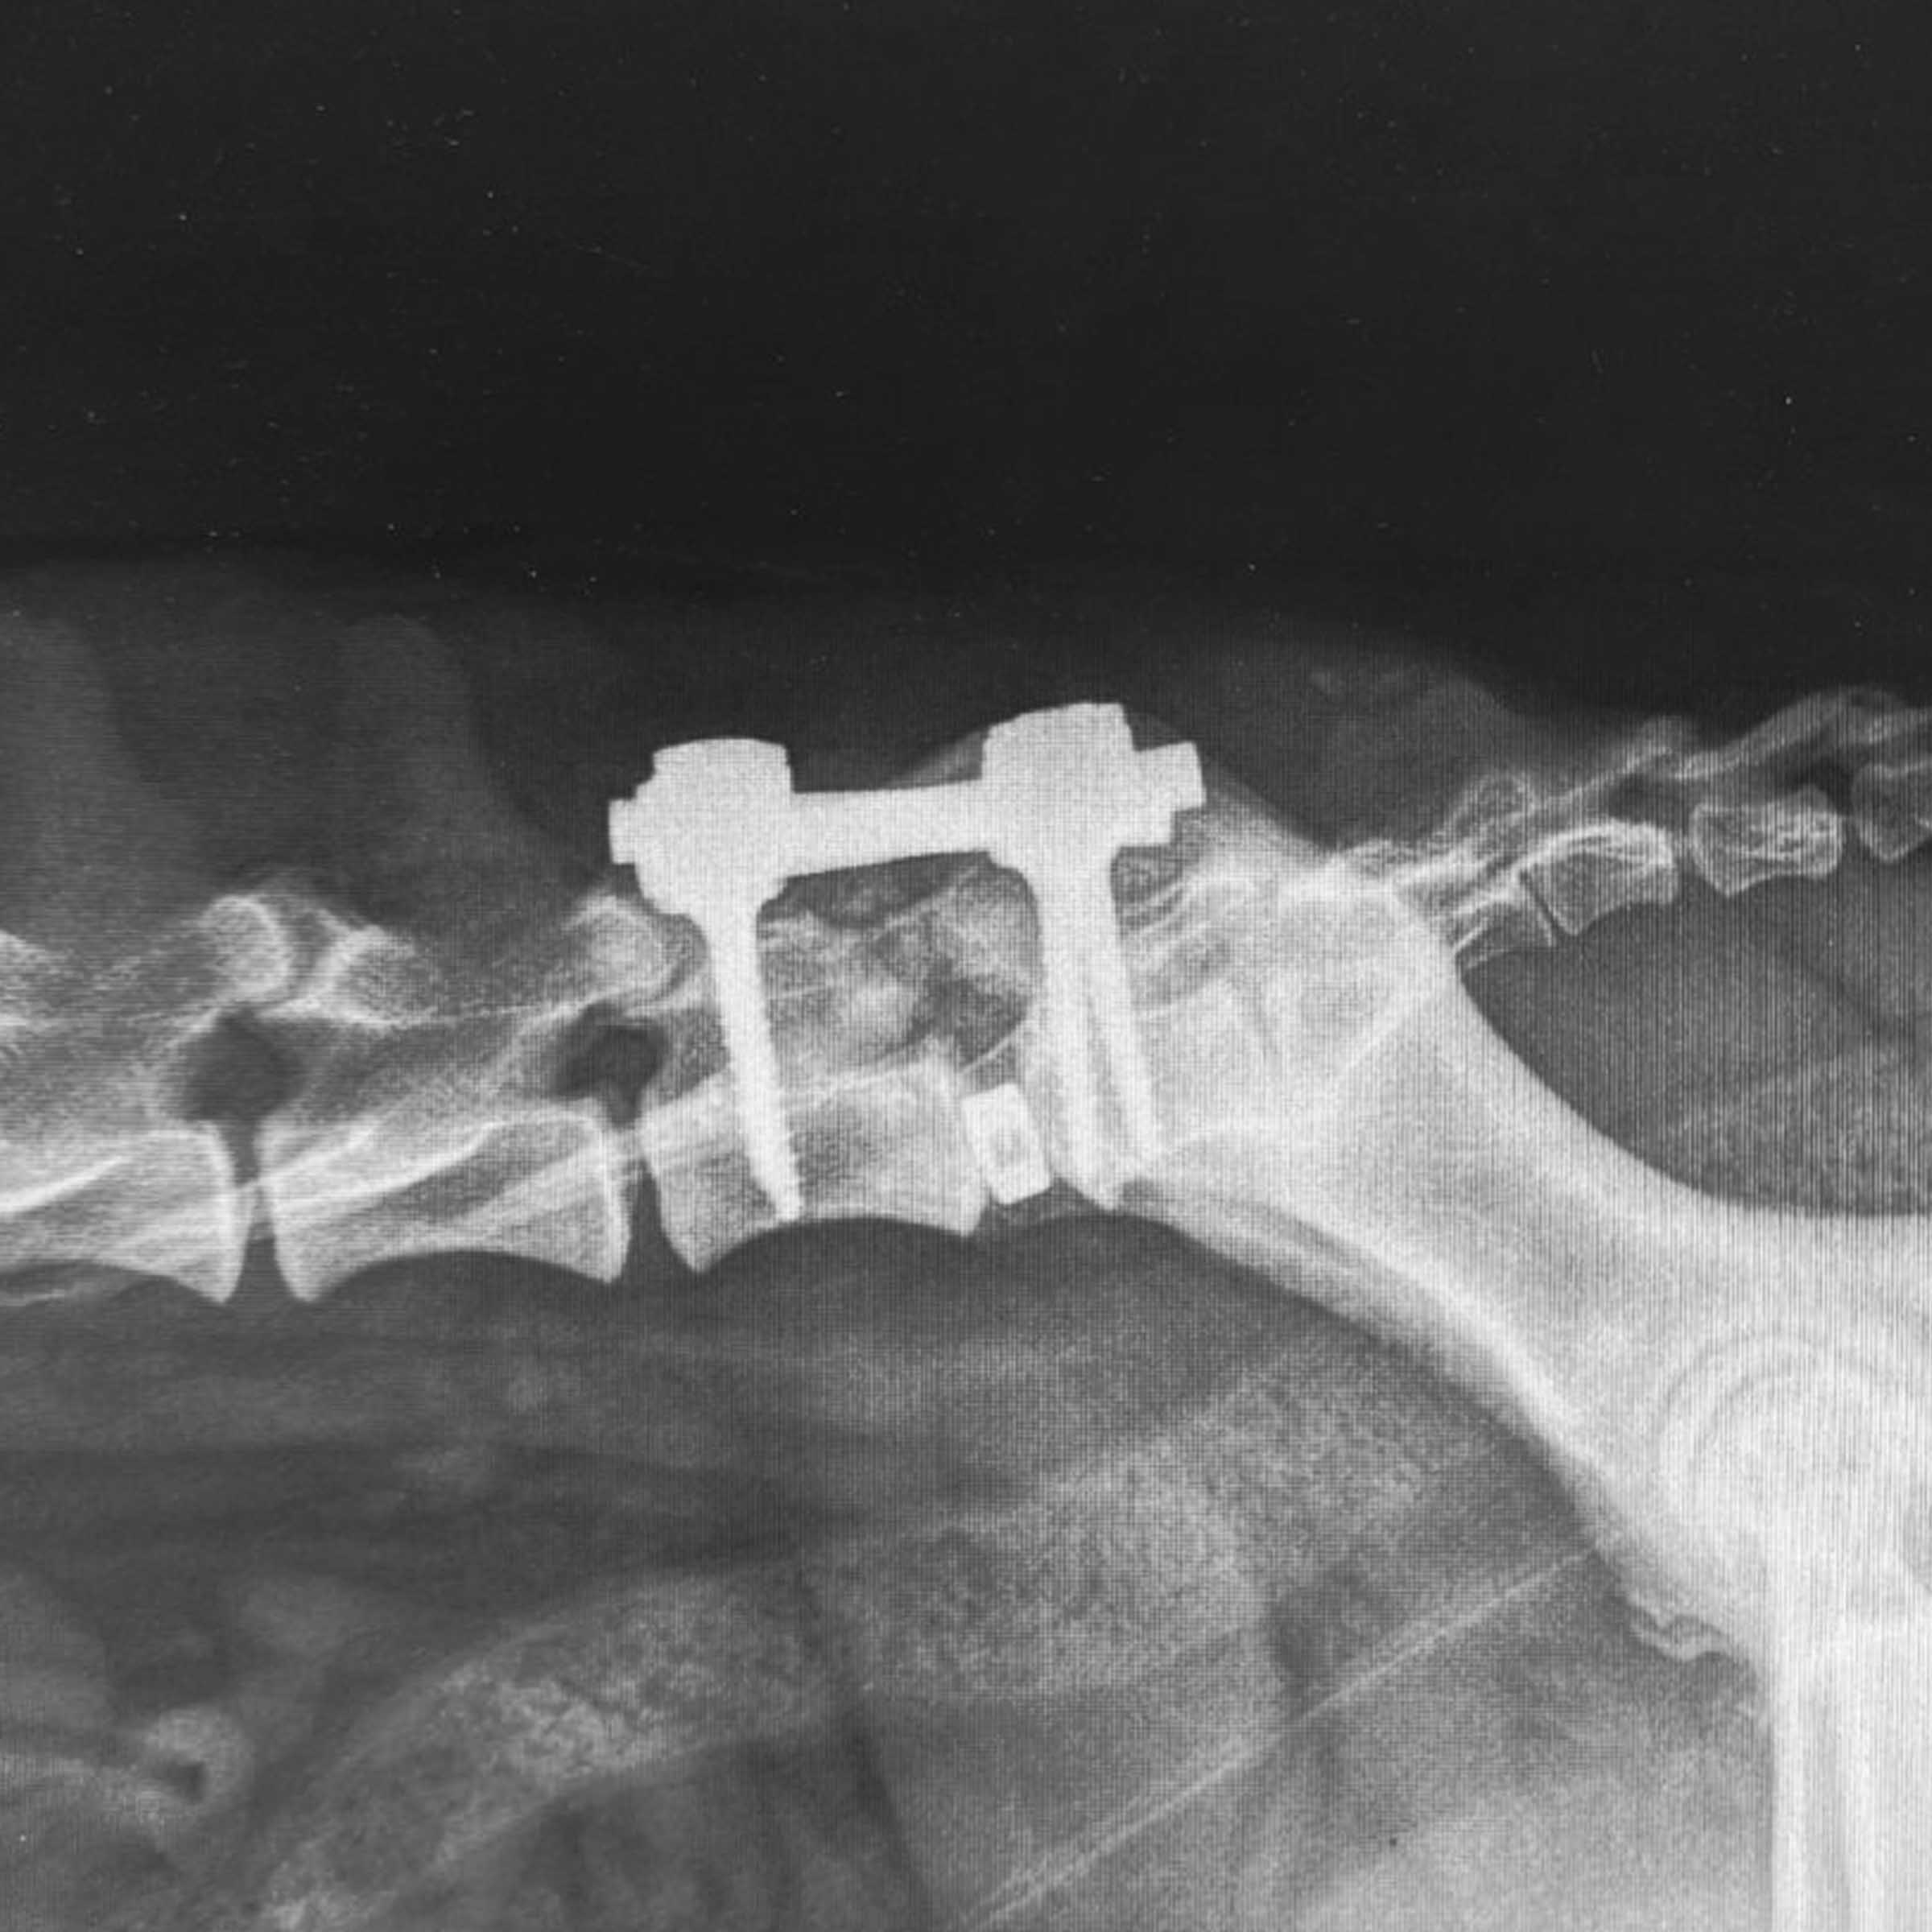

Case Overview In November 2025, Skeeter, a 14-week-old Doodle puppy weighing ...